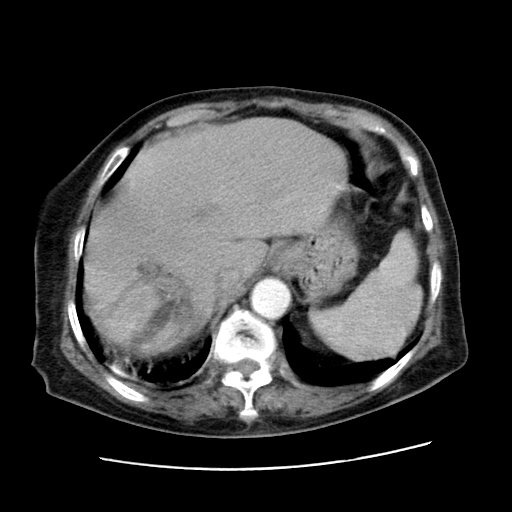

女,77.无不适

胆管扩张,壶腹部占位?

肝内胆管扩张,胆囊炎,胆囊窝积液。 右侧胸腔少量积液。

肝脏变异

肝右叶肝内胆管结石并肝内胆管扩张

胆总管扩张

右侧胸腔少量积液(也可能是胸膜增厚不过是什么都一样)

胆囊未见明显显影

肝右叶肝内胆管结石并肝内胆管扩张。另:慢性胆囊炎!胆囊窝积液!

肝右叶肝内胆管结石并肝内胆管扩张。胆总管下段梗阻,考虑壶腹部占位。

肝右叶肝内胆管结石并肝内胆管扩张。胆总管下段梗阻,考虑壶腹部占位。支持